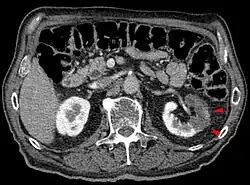

Los métodos diagnósticos son la ecografía, tomografía axial computarizada (TAC) o gammagrafía. La prueba de imagen más sensible y específica es la angiografía de la arteria renal. Sin embargo, esta prueba es invasiva y no se puede realizar en muchos casos.[2][3][5]